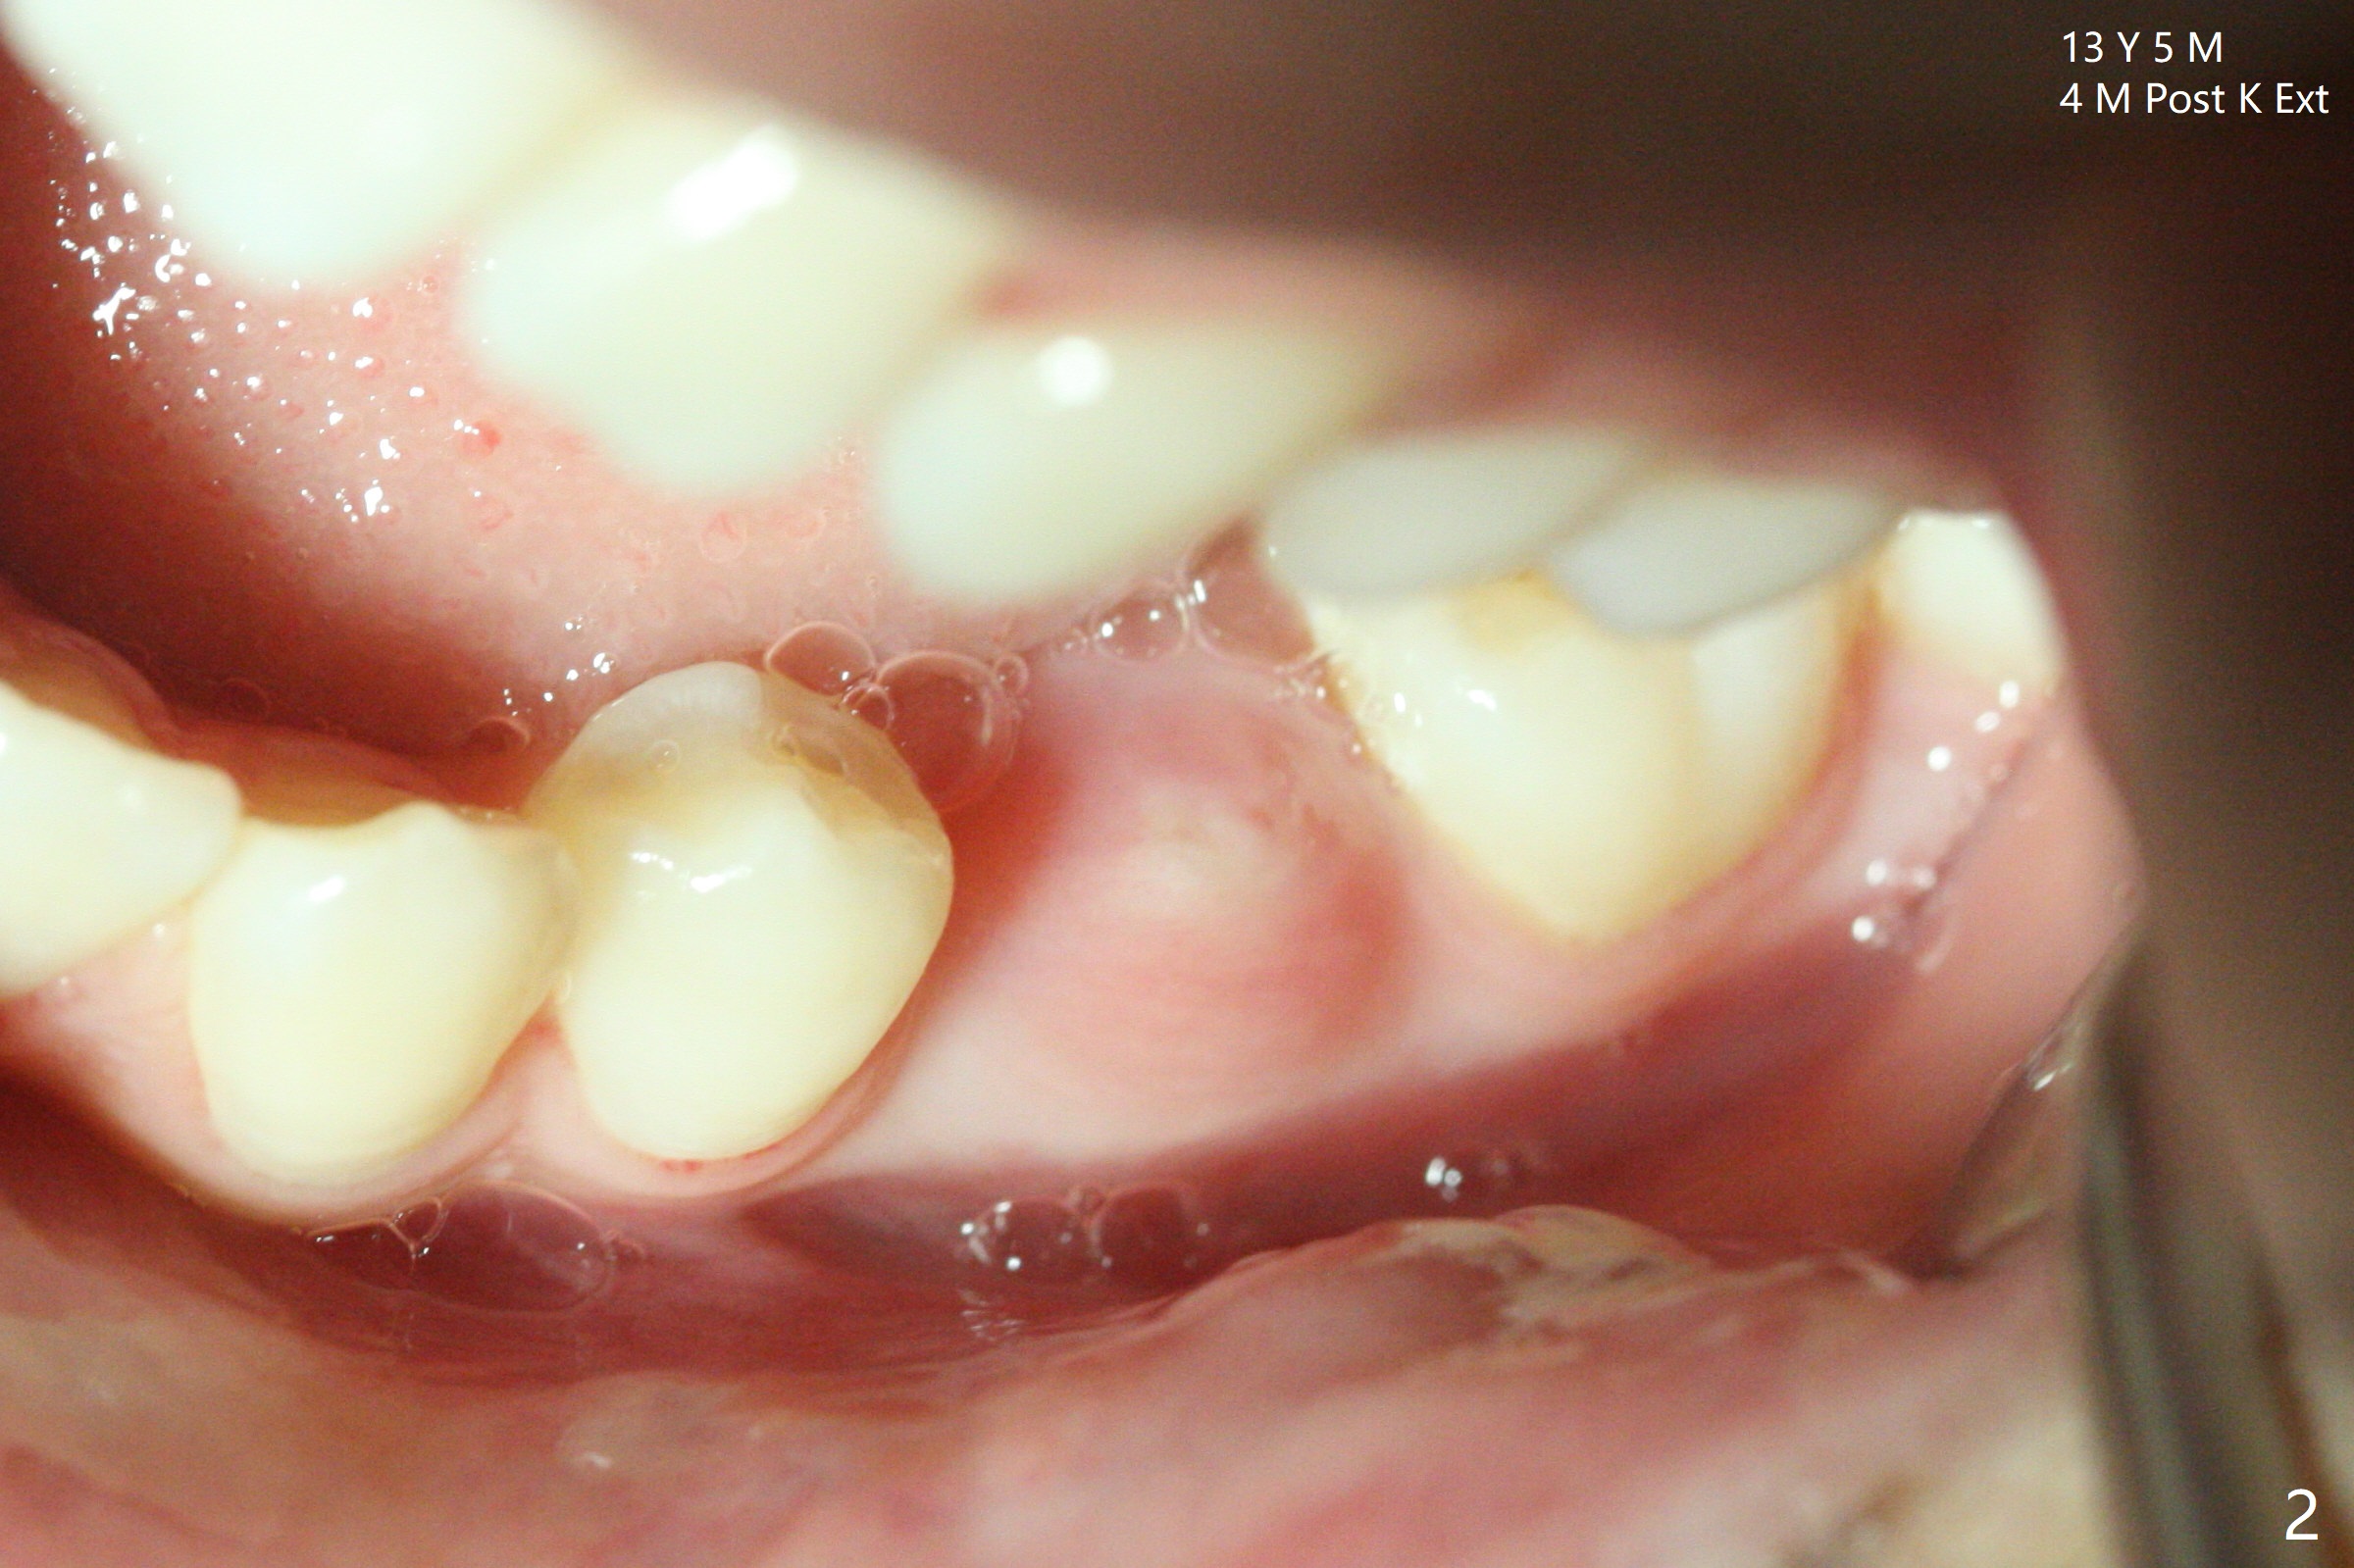

Delayed Eruption of #20

A 12-year-8-month-old woman retains K (Fig.1). Four months post extraction of K, the underlying permanent tooth is going to erupt (Fig.2).